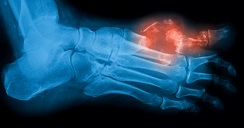

Asimismo, comentó que desde hace 16 años fue establecida la microcirugía en este servicio médico. Con ello, dicha área del hospital le da oportunidad a las personas con diabetes de que no pierdan sus piernas, pies y/o dedos de los mismos, ya que muchas personas con esta enfermedad crónico-degenerativa desarrollan pie diabético, que es una ulceración o destrucción de los tejidos profundos relacionada con alteraciones neurológicas y con distintos grados de obstrucción en las arterias de las extremidades inferiores. Normalmente se manifiesta cuando la diabetes no está siendo tratada correctamente.

Priego Blancas dijo que para concretar una cirugía de este tipo primero debe valorarse al paciente, subrayando que “lo recomendable es que no sea muy grande de edad, ya que a más edad más grave es el daño, para ver si se le puede evitar la amputación, que en ocasiones no es total, pero sí a 80 o 90 por ciento, es decir, si se necesitaba cortarle el pie se logra solo amputar un dedo”.

Y añadió que «antes todos se amputaban y ahora ya no, ahora digamos que estamos salvando 25 por ciento de las piernas que se iban a amputar, es algo maravilloso porque realmente quitándole lo frío de los números que le digan a una persona ya no te vamos amputar, es una maravilla y más para un diabético”.